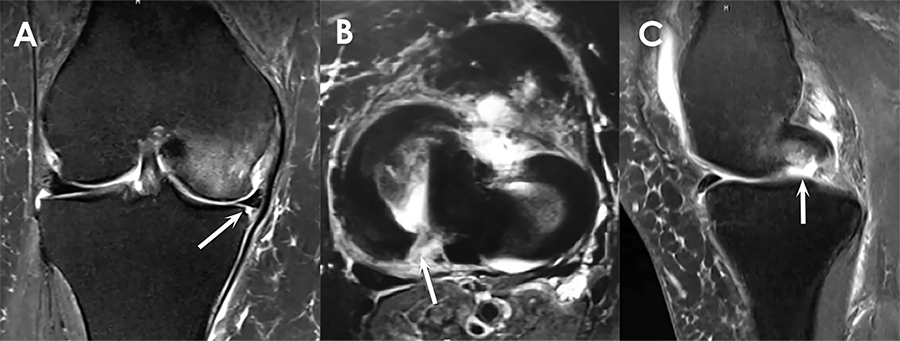

La RMN es un estudio clave en la lesiones de raíz meniscal, y debe ser utilizada como complemento de la historia clínica y del examen físico del paciente. Estudios previos han descripto que la RMN posee una sensibilidad del 93.3%, una especificidad del 100% y que posee valores predictivos positivos del 100% para detectar lesiones de raíz meniscal.9,28,29 Sin embargo, estudios recientes han sugerido que la precisión diagnóstica de las lesiones de raíz meniscal usando RMN es altamente dependiente de la calidad de la imagen y de la habilidad del radiólogo.22,30

En una revisión de la capacidad diagnóstica de la RMN, De Smet y col.9 sugirieron que ante la sospecha de una lesión de raíz posterior tres áreas deberían ser especialmente evaluadas: entre los tubérculos intercondíleos, a nivel del tubérculo lateral, y en el borde lateral de la eminencia tibial adyacente al tubérculo lateral. A su vez, deben evaluarse los planos coronales y sagitales, ya que la visualización de ambos planos proporcionó un incremento en la sensibilidad.9 Para lograr una mayor sensibilidad y especificidad deberían utilizarse secuencias en T2 con carga de peso ante la sospecha de dichas lesiones. Al examinar una RMN de un paciente con sospecha de una lesión de raíz meniscal hay una serie de signos diagnósticos ha tener en cuenta (fig. 5).

La extrusión meniscal medial, que se define como el desplazamiento parcial o total del menisco sobre el cartílago articular del platillo tibial, es un hallazgo que se correlaciona altamente con la presencia de una lesión de raíz meniscal.28,31,32 Estudios posteriores han demostrado que las extrusiones de menisco medial superiores a los 3 mm se encuentran vinculadas con la degeneración meniscal y las lesiones de raíz.8,32 Otro hallazgo importante a tener en cuenta es la presencia del signo de la imagen fantasma, definido como la ausencia de un segmento meniscal o el aumento en la señal del tejido meniscal en 3 o mas cortes sagitales continuos.8,33

Figura 5: Resonancia magnética nuclear mostrando una lesión de raíz meniscal. A) Corte coronal en T2 mostrando la extrusión del menisco medial en una rodilla derecha (flecha). B) Corte axial mostrando una imagen hiperintensa propia de una lesión radial a nivel de la unión del cuerno posterior con la inserción de la raíz meniscal en una rodilla derecha (flecha). C) Corte sagital mostrando una imagen fantasma del cuerno posterior del menisco externo en una rodilla derecha (flecha).